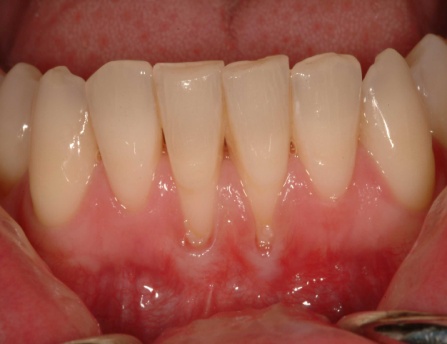

Gum grafts can be used to cover roots or develop gum tissue where it is missing due to gum recession. Gum grafting involves a procedure known as a connective tissue graft which is a delicate procedure where a small piece of gum tissue is taken from the palate or another donor site and transplanted to cover the exposed root.

This can be done for one or more teeth to even up your gum line and/or reduce root surface sensitivity. The benefits of gum grafting include: reducing further recession and bone loss, cover exposed roots to protect them from decay, reduce tooth sensitivity and improve the esthetics of your smile.